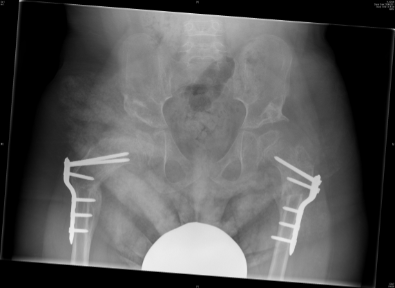

Για αποφυγή εμφάνισης εξάρθρωσης ισχίων ο γιατρός, ανάλογα με την κατάσταση του εκάστοτε ασθενούς, μπορεί να συστήσει συγκεκριμένες φυσιοθεραπείες ή ορθωτικά βοηθήματα, εκχύσεις βοτουλίνης ή χειρουργική επέμβαση για χαλάρωση των μαλακών μορίων. Όταν το εξάρθρημα της κεφαλής του μηριαίου ξεπερνά το 40% γίνεται χειρουργική επέμβαση με οστεοτομία μηριαίου και λεκάνης.

Οι εικόνες απεικονίζουν περιστατικό του Δρ. Ζένιου με εγκεφαλική παράλυση (non-walker), όπου παρουσιάστηκε με πόνο. Υποβλήθηκε σε χειρουργική επέμβαση για ανάταξη και των δύο ισχίων με οστεοτομία λεκάνης και μηριαίου.

Μετ-εγχειρητικά